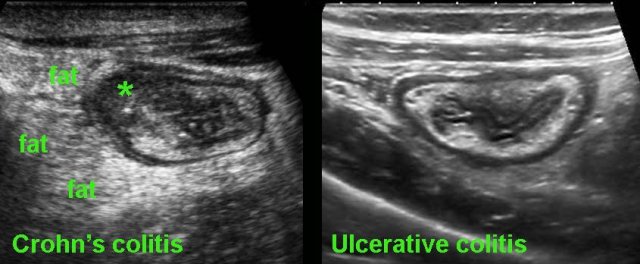

Finally, US may play a role in the differentiation of ulcerative colitis and Crohn’s colitis.

On clinical grounds and even with the help of endoscopy and biopsies, it can at times be difficult to differentiate Crohn’s colitis from ulcerative colitis.

In these cases, US can be of help: the demonstration of hypoechoic, transmural inflammation and the presence of non-compressible inflamed fat strongly favor Crohn’s disease.

Note the hyperechoic fatty tissue (fat) around the ileum, representing the inflamed mesentery and omentum, trying to wall off the imminent perforation.

In cases like this, the altered morphology and luminal narrowing may mimic malignancy.